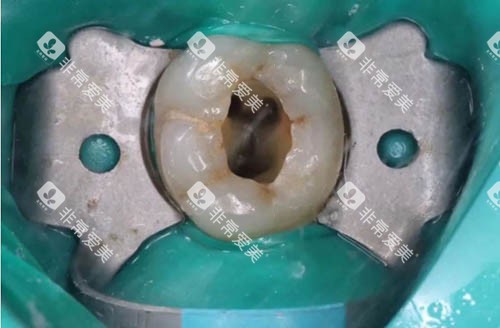

龋齿龋坏程度如何判断?附龋齿一度到五度真实图片,分级清晰易懂

龋齿是一种常见的口腔疾病,了解其龋坏程度的判断方法以及分级情况,对于及时治疗和预防龋齿的进一步发展至关重要。下面就为大家详细介绍。龋...